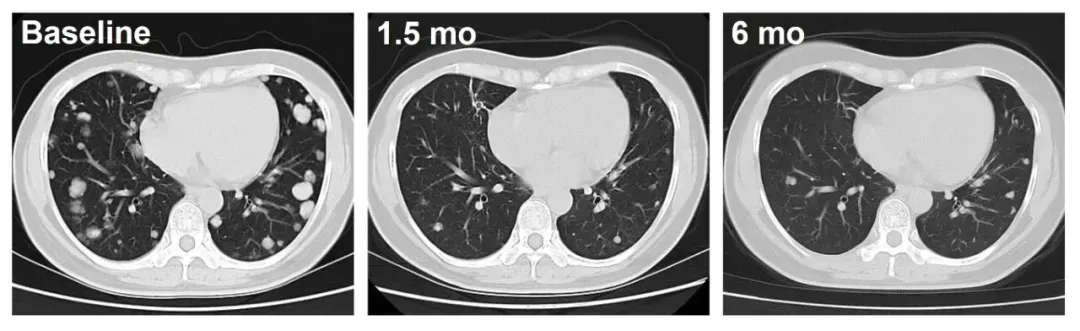

其针对经1-6线治疗失败的晚期肝癌(HCC)的IIT临床数据显示:两例患者(C023、C010)治疗后均实现肿瘤持续退缩的振奋疗效:患者C010(DL3)随访超12个月,肿瘤持续稳定缩小;患者C023(DL4)治疗1.5个月后,肺转移病灶深度应答,影像学可见肿瘤显著缩小(详见下图)。

▼C023号患者治疗前后影像学对比